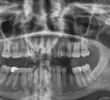

Çene Kistleri

Implant tedavisi